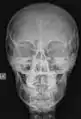

Radiografía

En este segmento de las imágenes médicas se puede encontrar desde los más simples exámenes de Rayos X hasta estudios complejos como el sistema digestivo. Las imágenes son obtenidas gracias a las diferentes capacidades que poseen los tejido de atenuar las radiaciones x, han sido utilizados en el ámbito médico desde su descubrimiento en 1895 por Wilhelm Conrad Röntgen y hasta nuestros días son ampliamente utilizados para realizar diagnósticos diferenciales en el área de la traumatología (pesquisa de fracturas, alteraciones de los huesos y malformaciones), a la vez permiten visualizar algunos órganos de menor densidad como los pulmones, en cuyo caso es posible detectar diferentes patologías que afectan a este órgano cono es el caso de la acumulación de polvos que al ser inhalados causan enfermedades definidas como silicosis. Todo estudio radiográfico está compuesto, a lo menos, por dos proyecciones lo que permite visualizar la estructura estudiada en dos planos perpendiculares.

Este método de adquisición de imágenes puede ser asociado con el uso de medios de contrastes, hidrosolubles sobre la base de bario o yodo dependiendo de la vía de administración, los que permiten realizar estudios específicos del sistema digestivo, urinario lo cual facilita el diagnóstico de una gran variedad de patologías. Desde su descubrimiento hasta la actualidad son muchas las transformaciones que han afectado a los equipos utilizados para tomar radiografías, todas ellas tendientes a reducir de manera considerable la exposición a radiaciones ionizantes tanto de los profesionales (médicos y tecnólogos médicos) que obtienen las imágenes, como la irradiación a la cual está expuesto el pacientes. En los últimos años, con la llegada de los equipos digitales, las dosis de radiación utilizadas para obtener un mismo examen se han reducido de manera considerable (la primera radiografía de una mano que se obtuvo demoró casi 15 minutos de exposición, hoy el mismo examen puede ser adquirido con apenas 20 a 30 milisegundos de exposición) lo que puede implicar una reducción de dosis considerable que podría llegar a ser más de 1000 veces menor.

Las imágenes digitales que se adquieren hoy en día, ya sea en radiología digital indirecta (CR) o directa (DR), presentan una gran ventaja debido a la potencialidad que su manejo informático ofrece, en el cual es posible sobre la base de una imagen adquirida aplicar diferentes herramientas como filtros que permiten mejorar el realce de los borde, suavizar, analizar el histograma y realizar análisis de la calidad de la imagen obtenida. Estas herramientas están disponibles en las consolas de procesado de imágenes de los equipos radiológicos, pero también existen programas dedicados como ImageJ que permiten realizar el análisis de las imágenes, ya sean de uso médico o no. Una de la funcionalidades de ImageJ es la posibilidad de "retocar" la imagen aplicando filtros como los que se observan en las siguientes imágenes en las cuales hemos aplicado a la imagen base de una radiografía de cráneo (al centro) un filtro que permite suavizar la imagen (Imagen 1) y luego a la misma imagen le hemos aplicado un filtro de reforzamiento de los bordes (Imagen 2).

Imagen 1

Imagen 2

Imagen basal